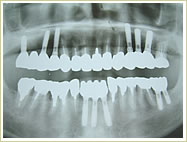

症例 68歳 女性 インプラント埋入数:1個 4本 画像拡大

治療前 治療後